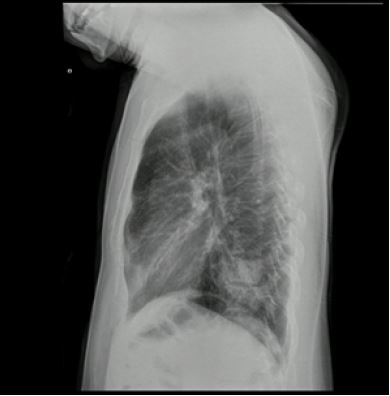

El caso corresponde a un hombre de 34 años de edad, natural de Valledupar y procedente de Bogotá, con diagnóstico de infección por VIH estadio 3 con adecuado control inmunovirológico, quien acudió al servicio de urgencias con un cuadro clínico de 4 días de evolución, caracterizado únicamente por singulto. No se encontraron datos positivos a la revisión por sistemas y no tenía otros antecedentes médicos relevantes. En el examen físico no se encontraron hallazgos significativos. Inicialmente, se manejó con haloperidol por vía intravenosa a una dosis de 2,5 mg cada 8 h durante 2 días, y posteriormente recibió metoclopramida a dosis de 10 mg por vía intravenosa cada 12 h durante 5 días sin presentar mejoría. Durante su estancia se registró un pico febril de 39 ºC. Dentro de los exámenes de extensión se evidenció leucocitosis y neutrofilia. La radiografía de tórax mostró una radiopacidad de ocupación alveolar en la base pulmonar izquierda en la proyección anteroposterior ( figura 1), también vista en la proyección lateral ( figura 2). Se consideró que el paciente se encontraba cursando una neumonía adquirida en comunidad, por lo cual se inició terapia antibiótica con ampicilina sulbactam y claritromicina. Sin embargo, ante un cuadro clínico poco claro, se decidió caracterizar el hallazgo radiológico mediante una tomografía de tórax de alta resolución, que confirmó que la ocupación alveolar se trataba de una consolidación ( figura 3). Tras 48 h de iniciada la terapia antibiótica, el singulto se resolvió. El informe final de los hemocultivos fue negativo y la evolución del paciente fue adecuada, por lo que se indicó egreso con control imagenológico en 6 semanas.